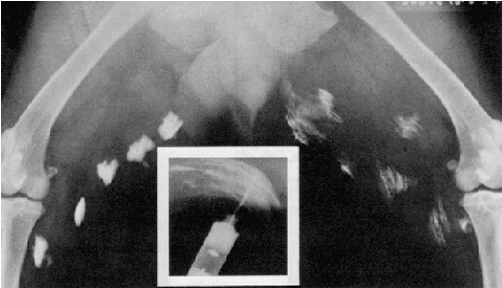

Atropine: Route of Administration |

In approximate order of preference, the following routes of administration can be used for the administration of atropine